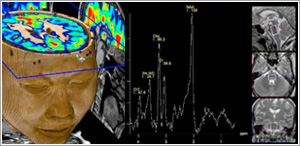

Neuro Imaging

MRI is considered the imaging modality of choice for most diseases affecting the central nervous system (brain and spine). Besides routine brain imaging, MRI is excellent at demonstrating diseases involving the internal auditory canals, pituitary gland, and orbits. Diffusion MRI is currently the earliest imaging modality for detecting acute stroke.

MR Spectroscopy (MRS)

MRS is a relatively new clinical procedure that allows detection of biochemical abnormalities within the brain. It is generally performed in addition to an MRI scan